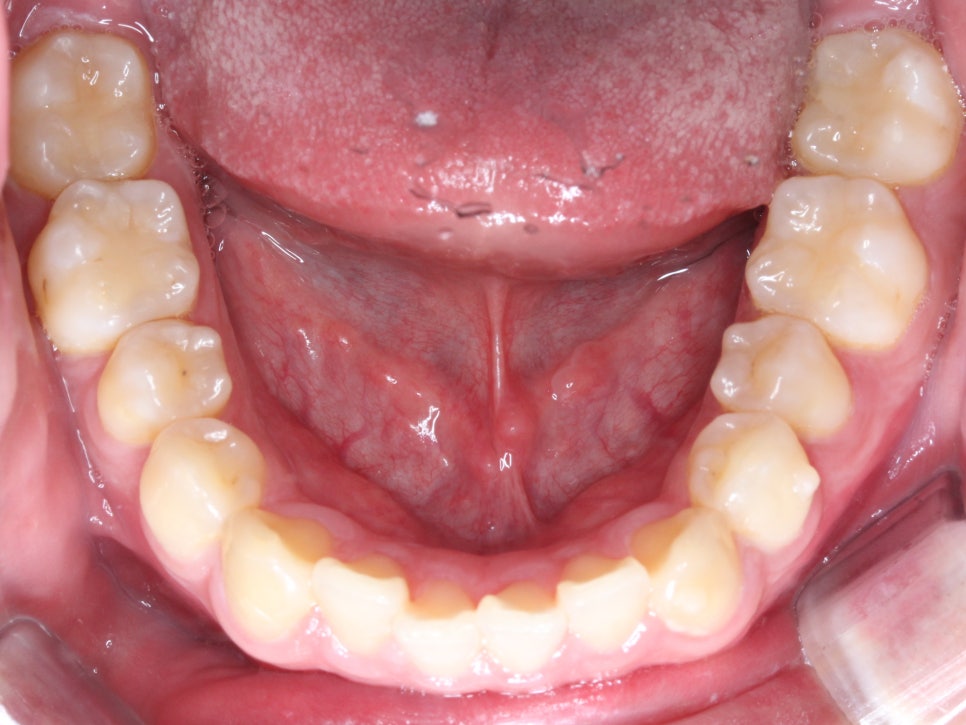

상악과 하악의 안쪽면 사진에서도

치아의 총생이 발견되었습니다.

상악의 경우 앞니의 나비치아 성향이 두드러지는 반면

하악의 경우에는 중절치의 미세한 돌출과

측절치의 이탈로 인해 총생이 발견되네요.

상악과 하악의 안쪽면 역시

가지런하게 배열된 모습이네요

특히 치아 크라우딩이 발견되었던

하악의 전치부가 예쁘게 정돈된 모습이죠?